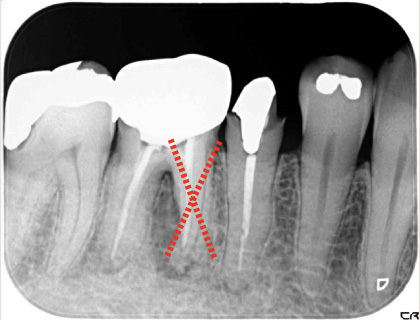

二本や三本に分かれている根を分割して残す治療

タービンで歯を切断します。

状態の悪い歯根のみを抜歯します。

ブリッジを装着します。

左から二本目の歯は2根に分かれていて手前(バツ印)の根がダメになっています。

ダメになっている根を抜いて手前の根とブリッジでつなぎました。